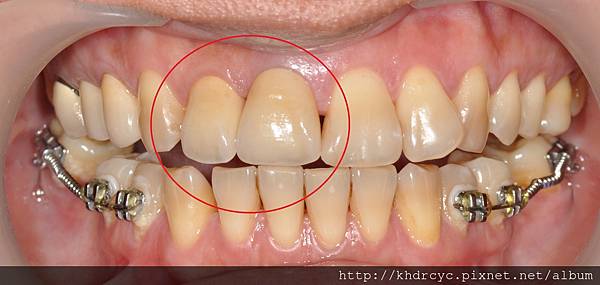

95%以上都是理面套的牙齒出問題

包括蛀牙 牙周病 根管問題 斷裂等等

假牙本身材質耐的住

大部分牙齒壞掉須要重新治療甚至拔牙時

假牙本身都還好好的需破壞掉才拆得起來

所以假牙能夠用多久

關鍵就在於 [能不能維護裡面套的牙齒]